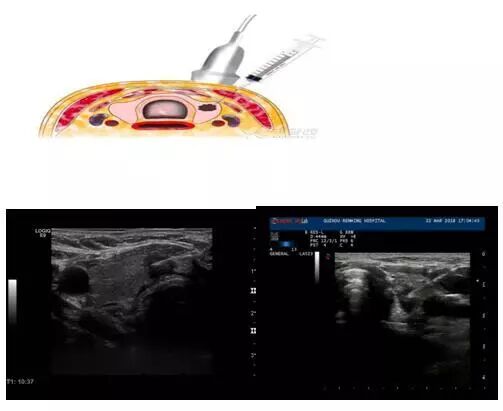

??? 在超聲直視引導(dǎo)下,經(jīng)皮穿刺甲狀腺、乳腺、淋巴結(jié)等部位獲取病變區(qū)域組織條或細(xì)胞成分,送病理學(xué)檢查,是術(shù)前獲取病理診斷、鑒別腫瘤良惡性的最主要方法。由于穿刺針?lè)浅<?xì),僅1mm左右,是非常安全有效的一種診斷手段。

???? 那么,什么時(shí)候需要穿刺呢?一般而言主要是兩種情況,第一種情況是甲狀腺結(jié)節(jié)TI-RADS 分類(lèi)4類(lèi)及以上,乳腺腫塊BI-RADS分類(lèi) 4類(lèi)及以上,需要行超聲引導(dǎo)下穿刺活檢以明確病變性質(zhì)。第二種情況是甲狀腺結(jié)節(jié)、乳腺腫塊準(zhǔn)備消融治療前需常規(guī)行穿刺活檢獲取病理診斷。

??? 超聲科醫(yī)師的角色是根據(jù)超聲表現(xiàn)確定是否要對(duì)甲狀腺結(jié)節(jié)進(jìn)行FNAB(細(xì)針穿刺活檢),超聲介入科醫(yī)師則是實(shí)行在超聲引導(dǎo)下進(jìn)行穿刺活檢技術(shù)。